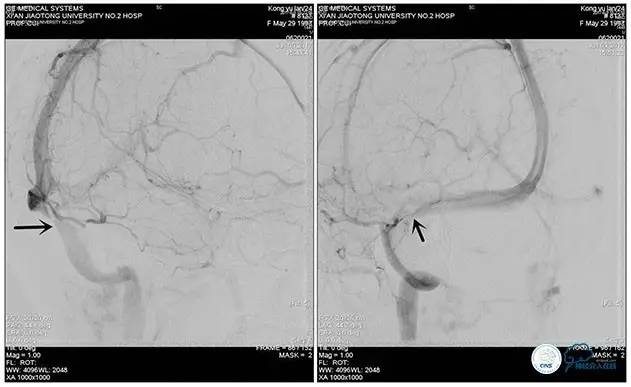

术中造影

5ml/s,总量8ml,压力100~150

手术方案

1、6mm×20mmAviator球囊(Cordis)分段对狭窄部位进行扩张。

2、植入7mm×40mmPrecise自膨支架。